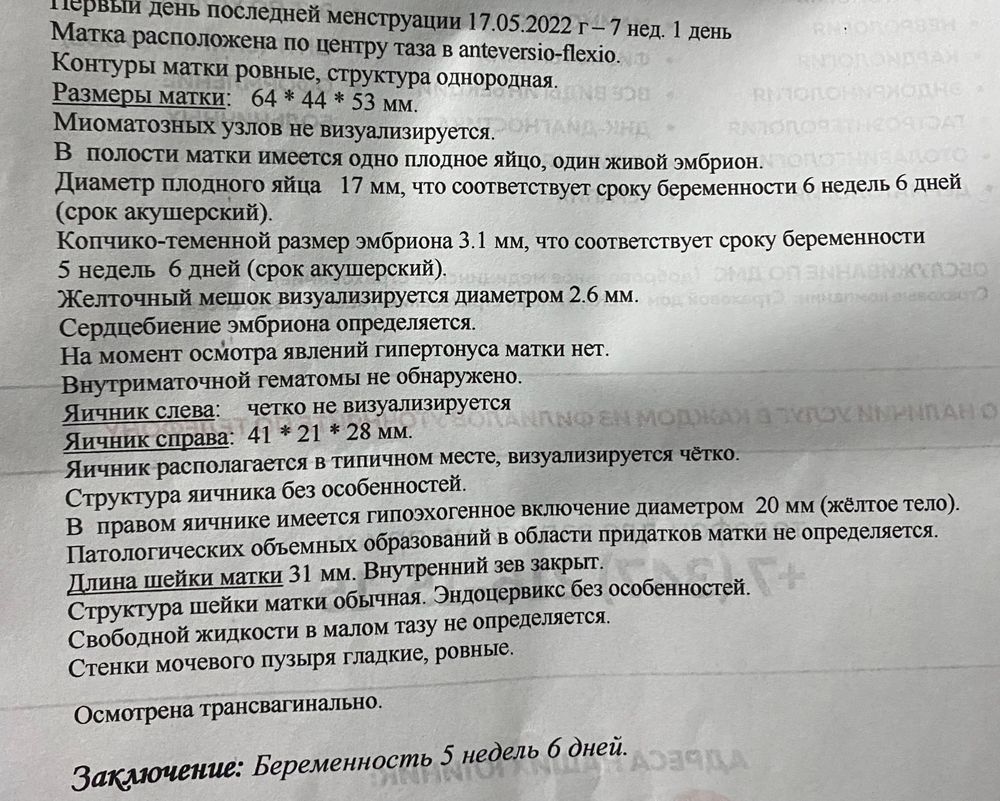

вот результаты узи

Кама, Если я правильно понимаю, у Вас 5,6 - это эмбриональный срок, а по месячным (акушерский) - 7 нед 1 день 😊

Настёна, не знаю 🤷🏻♀️ У меня 3 разных срока стоит в заключении узи, посмотрите пожалуйста: по месячным 7 недель и 6 дней, по плодному яйцу 6 недель и 6 дней, а по размеру эмбриона 5 недель и 6 дней 🙄🙄🙄 Но знаю что овуляция была 8 июня +1-2 дня)